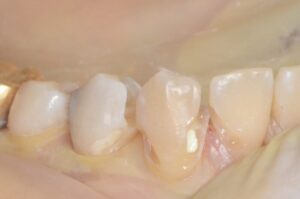

上の写真は適切に充てんされたアマルガム充填の例です。アマルガムが他の材料と比較して優れている理由には次の3つがあります。

まず、虫歯は必ず下掘れになっているため、インレーなどの修復材料では歯を多く削りすぎてしまうからです。歯を削りすぎると、かみ合わせの面を人工的に作らなければならず、かみ合わせを狂わせてしまう可能性が大きくなるからです。アマルガムはかみ合わせの面の歯の切削量を最小限にしてくれます。

次に、臼歯部には強い咬合力(噛む力)が加わるため、十分な強度が必要になります。最近よくつかわれるレジン(樹脂)は、見た目は白くてよいのですが、強度が咬合力に対して不十分であったり、吸水性(水を吸う性質)があったり、材料自体に抗菌性がありません。一方アマルガムには、金属としての十分の強度と、強い抗菌性があるため、虫歯が拡大しにくいのです。

最後にアマルガムには歯に詰めた後に膨張する性質があるため、歯に完全に適合し、歯と材料との間に空間(死腔と呼ばれる)を作ることがなく、虫歯の再発が極めて少ないです。ただ水銀が含まれている(無機水銀ですので人体には安全です)環境への問題から使用しない人もいますが、歯を長持ちさせるためには今でも欠かせない材料です。